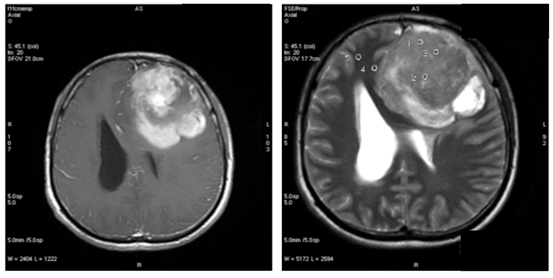

In our study showed that tumor volume as suggested by Hale et al. as the strongest predictor of atypical meningioma, didn’t always correlate with meningioma grade. In our samples there were 6 (37.5%) meningioma WHO grade I with tumor volume more than 50 cm3, with the biggest volume 252.4cm3 (Figure 1) and 1(33%) of atypical meningioma (WHO grade II) with tumor size 28.5 cm3. Hale also suggested that peritumoral edema as predictor of higher grade meningioma. In our study we found 1 case of anaplastic meningioma (WHO grade III) with mild edema and conversely, 44% of meningioma WHO grade I with severe edema (Figure 2). In that study also found that tumor along the falx and convexity were more often atypical than in skull base or posterior fossa. In this study, samples of meningioma WHO grade I mostly (37.5%) located in convexity, 25% in falx and in atypical meningioma WHO grade II turned out 67% located in skull base (Figure 3). That study also found that tumor necrosis was associated with an increased risk for atypical meningioma. In this study, we found 67% of atypical meningioma WHO grade II without tumor necrosis and 44% of typical meningioma WHO grade I with tumor necrosis (Figure 4). 1 case of anaplastic meningioma (WHO grade III) in our study had large tumor volume (>50 cm3), located in convexity and with tumor necrosis although there was one predictor that didn’t suit which in this case had mild peritumoral edema (Figure 5).

Figure 5 Male, 21 y.o, tumor vol 190.2 cm3 with mild peritumoral edema, located at left frontoparietal convexity, tumor necrosis (+), turned out to be meningioma anaplastic type, WHO grade III.